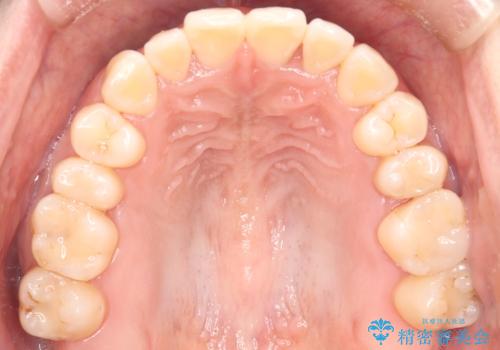

- 上の前歯の捻れを主訴に来院されました。

前歯の捻れとがたつきを改善するために、IPR(歯と歯の間を削る処置)と歯列拡大をすることで歯並びを整えていく治療計画を立てました。

かみ合わせを整えるためにゴム掛けも行いながら、治療していきました。

患者様にマウスピースの使用とゴム掛けを頑張っていただいたおかげでリファイメント(マウスピースの再発注)も1回で終了することができました。